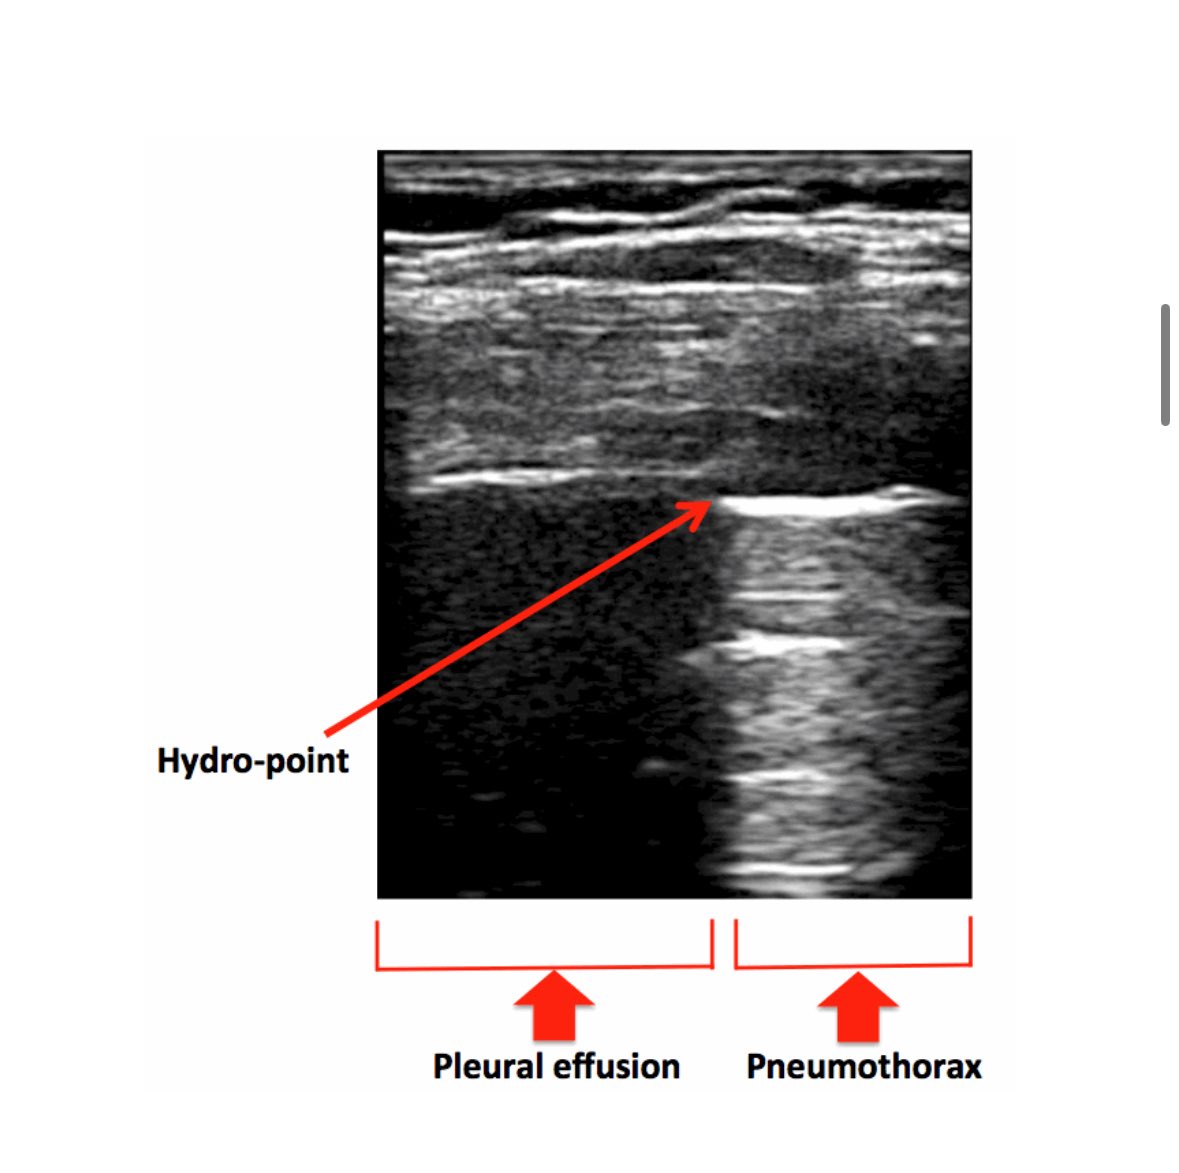

#POCUS muestra derrame pleural complejo, heterogéneo, con ecos internos y fibrina, hallazgos compatibles de empiema.